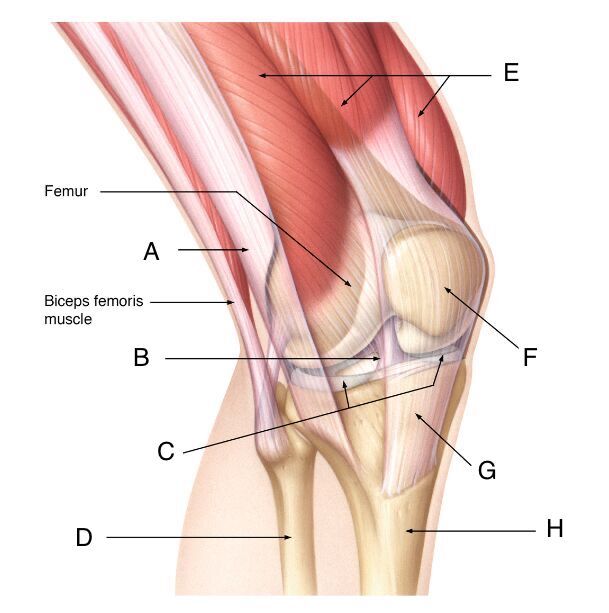

Name A-H

A

A- iliotibial band

B- Anterior cruciate ligament

C- Menisci

D- Fibula

E- Quadricep muscles

F- Patella

G- Patellar ligament

H- Tibia